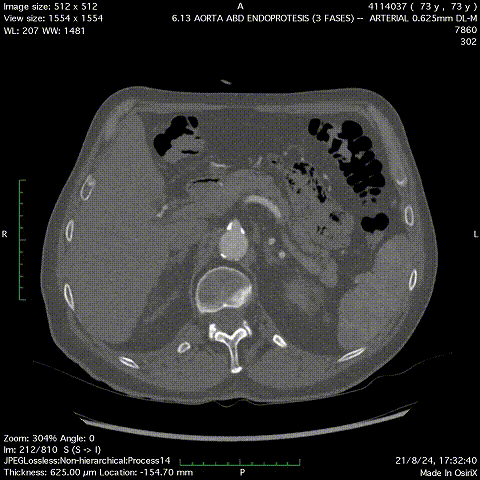

患者男性,73岁,腹主动脉瘤,高血压、血脂异常、慢性肾病。右侧股动脉中度钙化,直径5.4mm,入路面临挑战。选用Minos覆膜支架进行治疗,手术过程顺利,术后1个月的CT扫描显示无内漏且肢体通畅。该案例体现了Minos覆膜支架的Low Profile的低外径输送系统能够在狭窄和迂曲的动脉中顺利操作,为因血管条件不佳而不适合传统EVAR的患者提供了新的治疗选择。